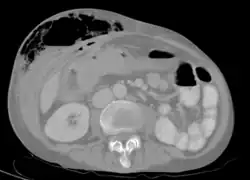

Abdominal CT scan with right colocutaneous fistula and associated subcutaneous pneumatosis | |

In anatomy, a fistula (pl.: fistulas or fistulae /-li, -laɪ/; from Latin fistula, "tube, pipe") is an abnormal connection (i.e. tube) joining two hollow spaces (technically, two epithelialized surfaces), such as blood vessels, intestines, or other hollow organs to each other, often resulting in an abnormal flow of fluid from one space to the other.[2][3][4] An anal fistula connects the anal canal to the perianal skin. An anovaginal or rectovaginal fistula is a hole joining the anus or rectum to the vagina. A colovaginal fistula joins the space in the colon to that in the vagina. A urinary tract fistula is an abnormal opening in the urinary tract or an abnormal connection between the urinary tract and another organ. An abnormal communication (i.e. hole or tube) between the bladder and the uterus is called a vesicouterine fistula, while if it is between the bladder and the vagina it is known as a vesicovaginal fistula, and if between the urethra and the vagina: a urethrovaginal fistula. When occurring between two parts of the intestine, it is known as an enteroenteral fistula, between the small intestine and the skin it is known as an enterocutaneous fistula, and between the colon and the skin as a colocutaneous fistula.[3]